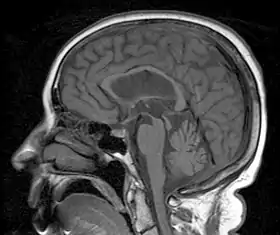

| A person with progressive dementia, ataxia, and incontinence. A clinical diagnosis of normal-pressure hydrocephalus was entertained. Imaging did not support this, however, and on formal testing, abnormal nystagmus and eye movements were detected. A sagittal view of the CT/MRI scan shows atrophy of the midbrain, with preservation of the volume of the pons. This appearance has been called the "hummingbird sign" or "penguin sign". Also, atrophy of the tectum is seen, particularly the superior colliculi. These findings suggest the diagnosis of progressive supranuclear palsy.[1] | |

Magnetic resonance imaging (MRI) is often used to diagnose PSP. MRI may show atrophy in the midbrain with preservation of the pons giving a "hummingbird" sign.[27]